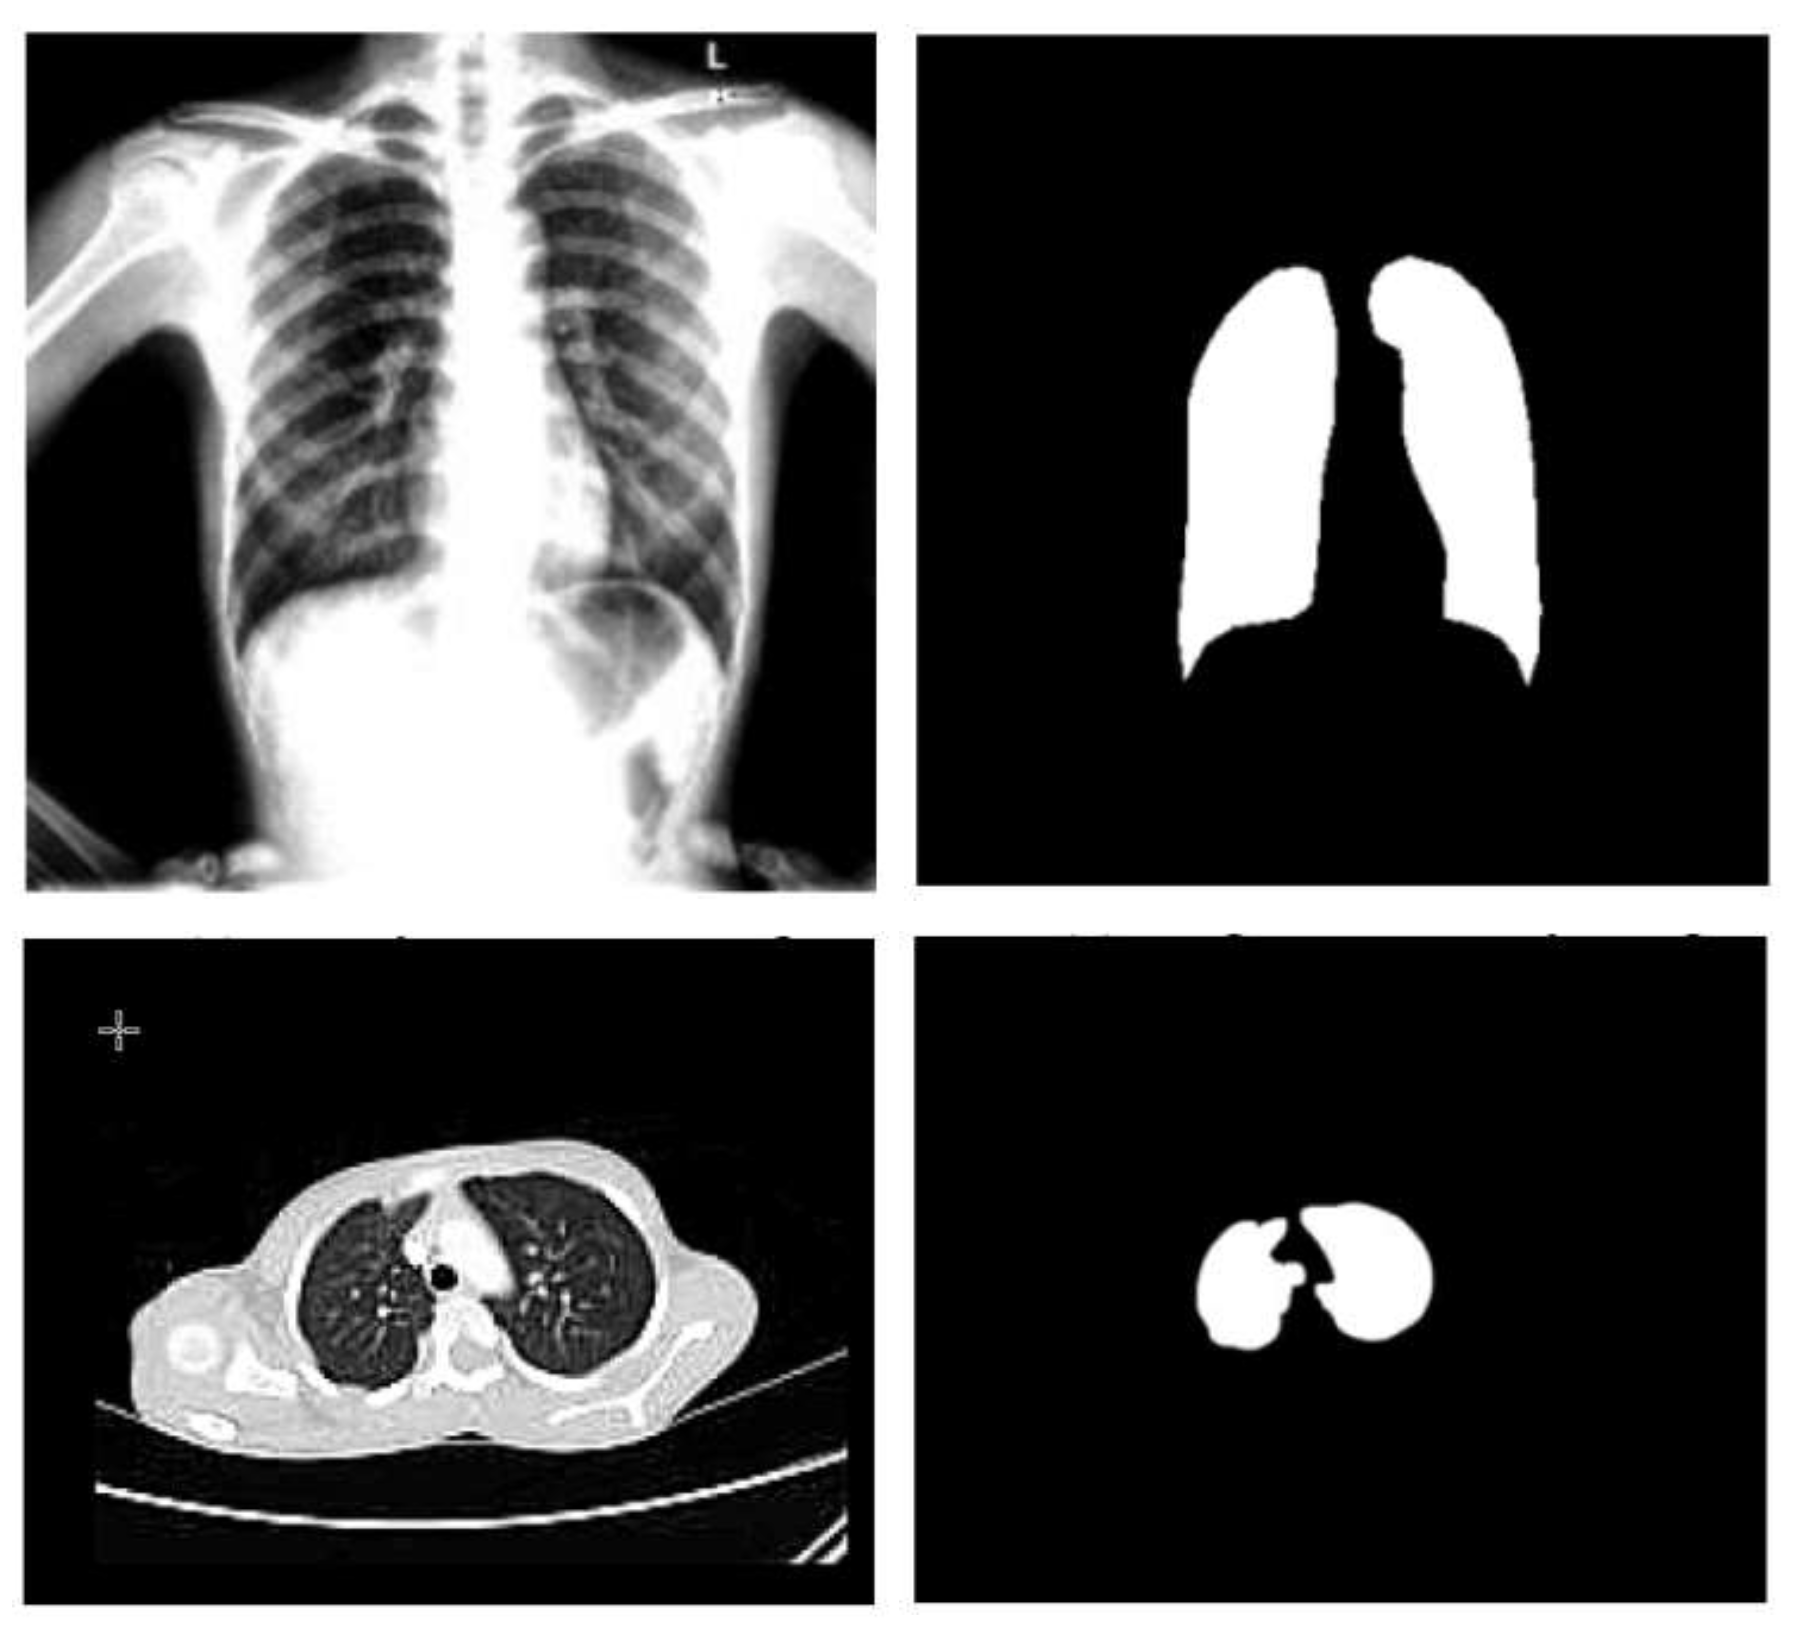

The cluster center is now randomly chosen, indicated by the letter C. Next, the fuzzy center is calculated, and finally, the cluster center is updated. A centroid must be determined for each cluster to update the cluster center. It is crucial to compute the centroid by averaging all the x- and y-axes. It is essential to take the mean of all the points in each cluster to re-compute the new cluster center. Sample X-ray and CT images before (on the left) and after (on the right) the segmentation process are shown in Figure 3.

Figure 3.

Sample X-ray and CT images before and after the segmentation step.